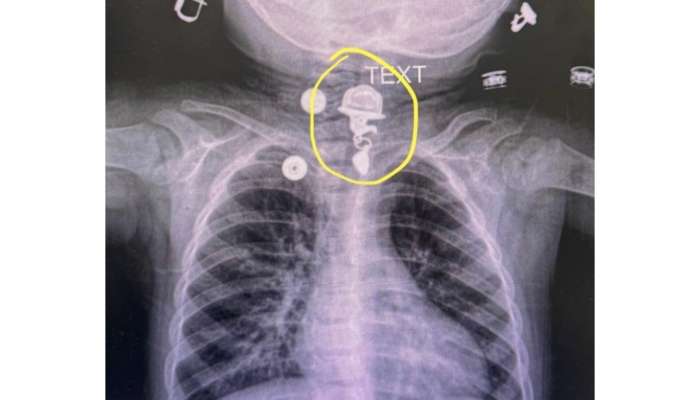

Həkimlər